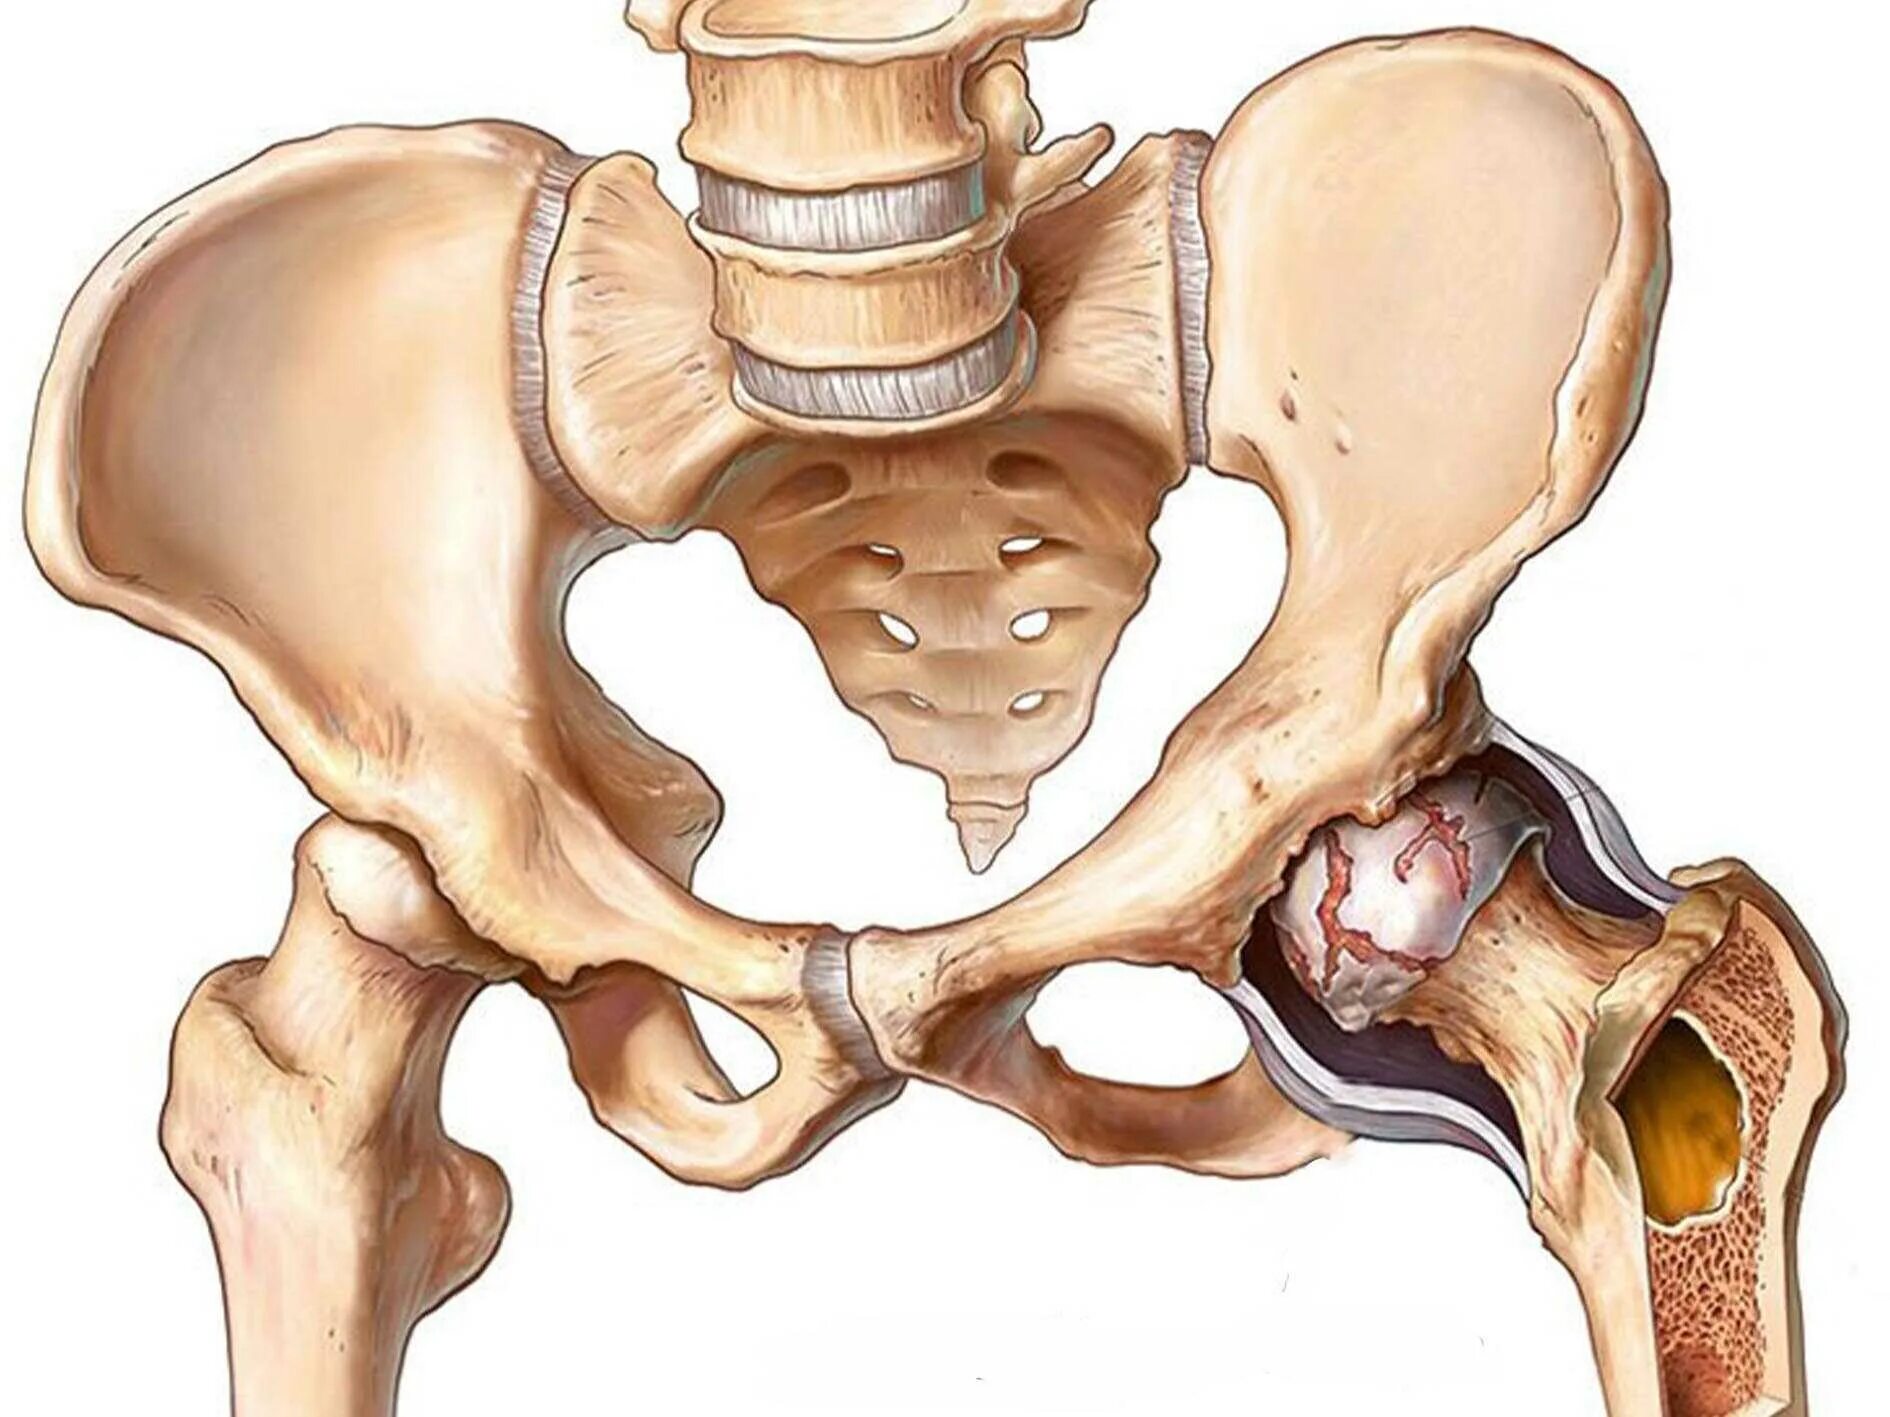

Тазобедренный сустав это